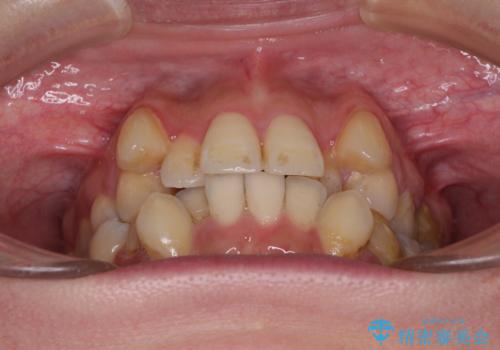

【モニター】上下の八重歯を治したい ワイヤー装置による矯正治療

- 上下前歯のデコボコを気にして来院された患者様です。

デコボコが強いため、非抜歯で矯正をすると出っ歯仕上がりとなるため、上下左右の第一小臼歯4本を抜歯することとしました。